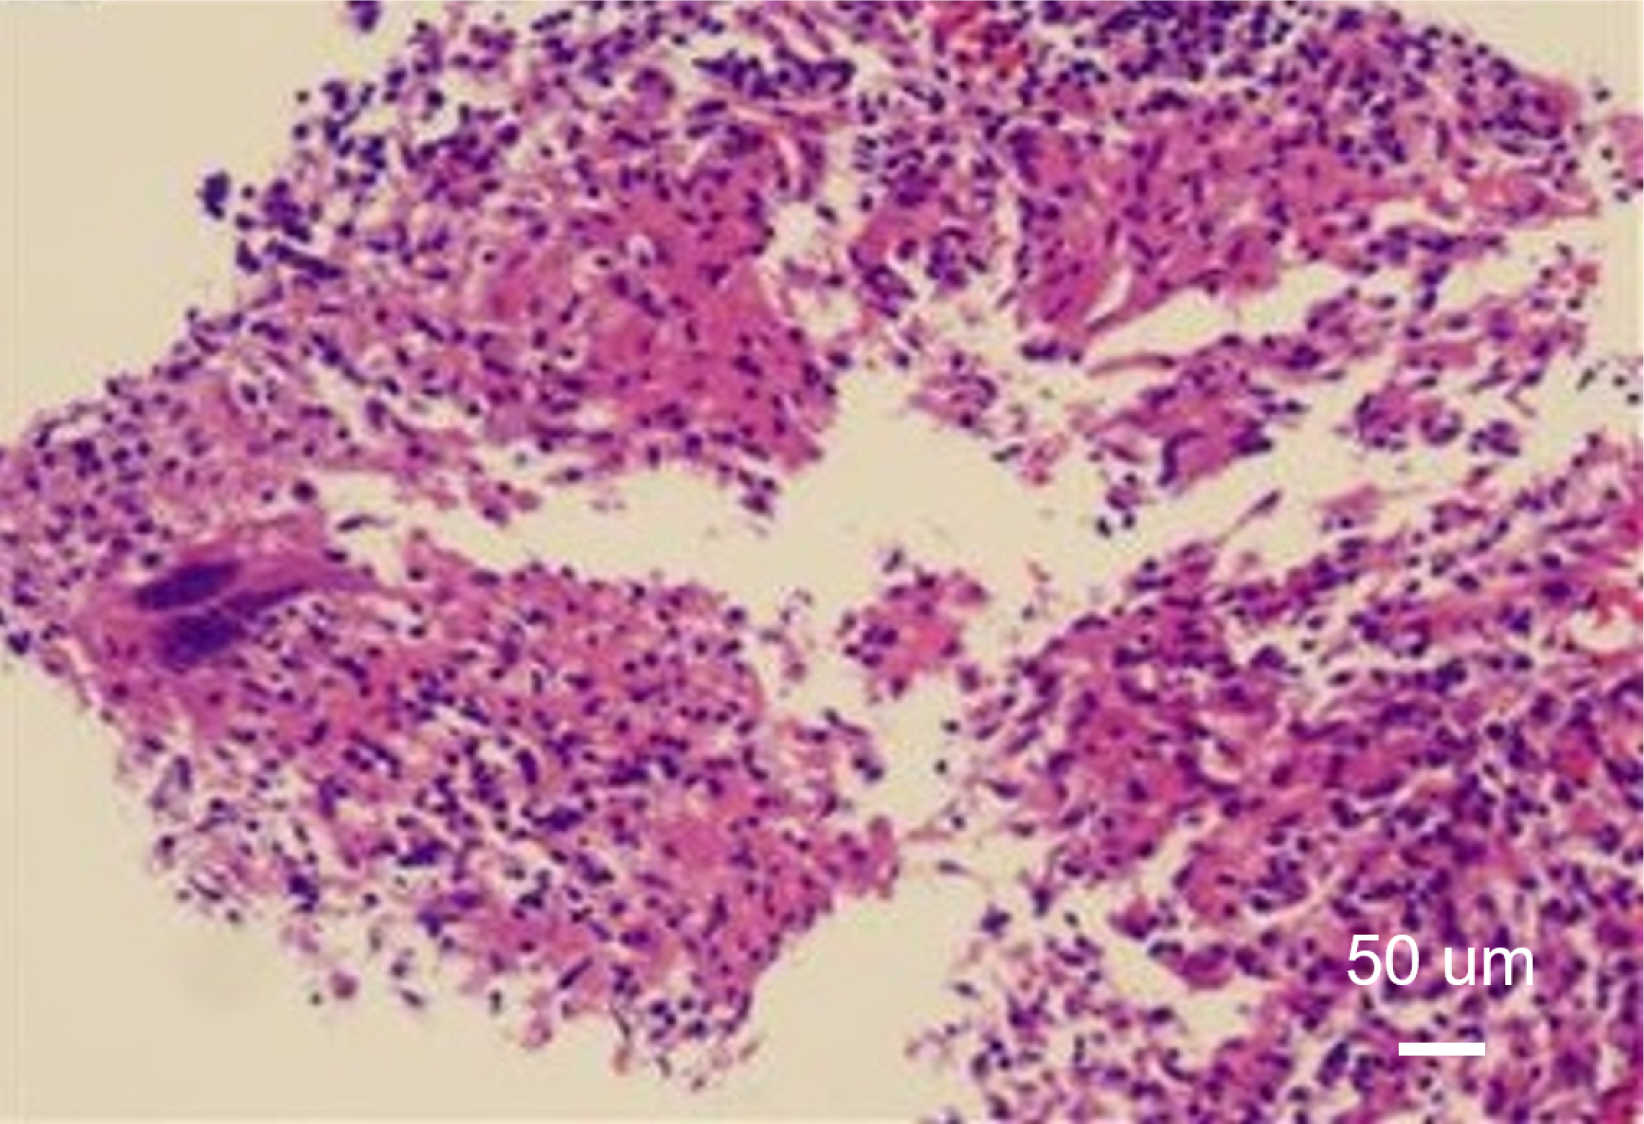

Figure 3 Pathological images of liver biopsy specimens (× 100).

Scattered granulomatous nodules with small areas of focal necrosis observed within the lesion tissue.